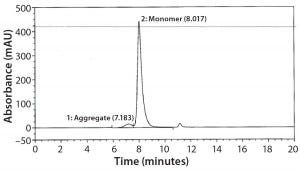

Figure 2: Size-exclusion chromatography with ultraviolet detection (SECUV)

data

SEC Analysis: All SEC data (pre- and postfill, and upon storage) show comparable percentages of high–molecular-weight (HMW) species for both the glass and Advasept vials (Figures 2–4).

Figure 3: Magnified size-exclusion chromatogram